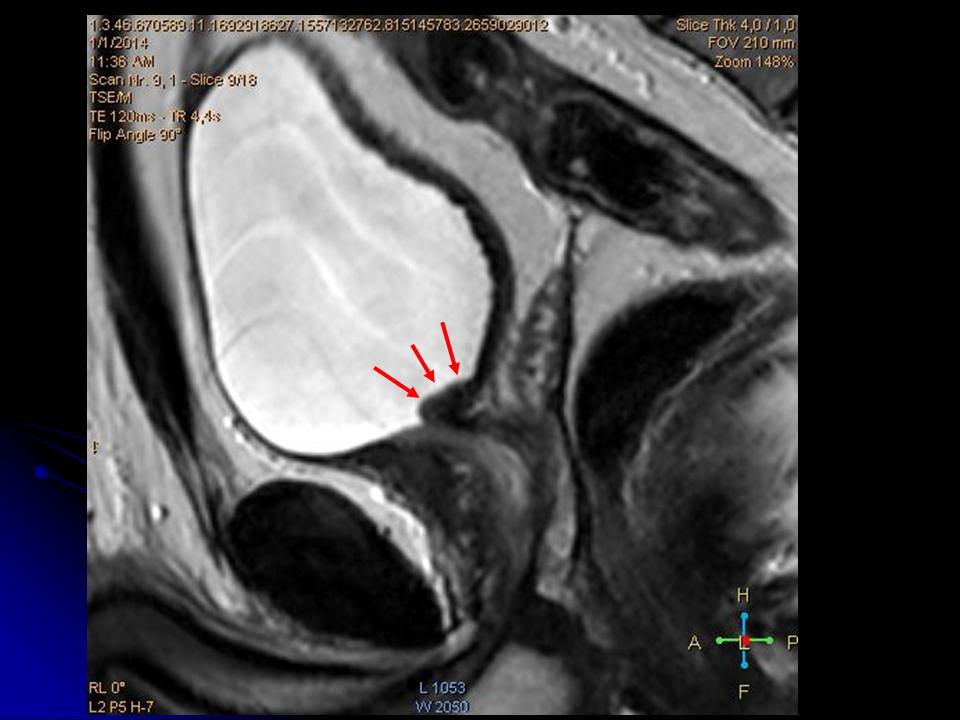

Изображения КТ конкрементов мочевого пузыря